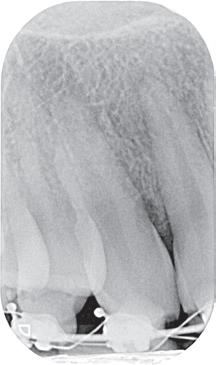

Een 67-jarige patiënt (ASA I) wordt doorverwezen voor een endodontische behandeling op tand 34 om-

wille van necrose en de daaruit volgende symptomatische apicale parodontitis. Na klinisch onderzoek kan een buccale cervicale klasse V composietrestauratie met randlekkage en secundaire cariës weerhouden worden. De tand is intact op het occlusaal oppervlak (afbeelding 1a, b, c). Pre-operatieve peri-apicale radiografie toont een apicaal letsel met een normaal verloop van het wortelkanaal (afbeelding 2a). Eén jaar follow-up toont volledige apicale genezing aan en klinisch zijn er geen tekenen van secundaire cariës.

De keuze om gebruik te maken van de reeds aanwezige restauratie ligt in dit geval voor de hand (Restorative and Caries-Driven access cavity) (afbeelding 3a), maar hierbij dient rekening gehouden te worden met de locatie van het kanaal ten opzichte van het buccale oppervlak (afbeelding 4a).